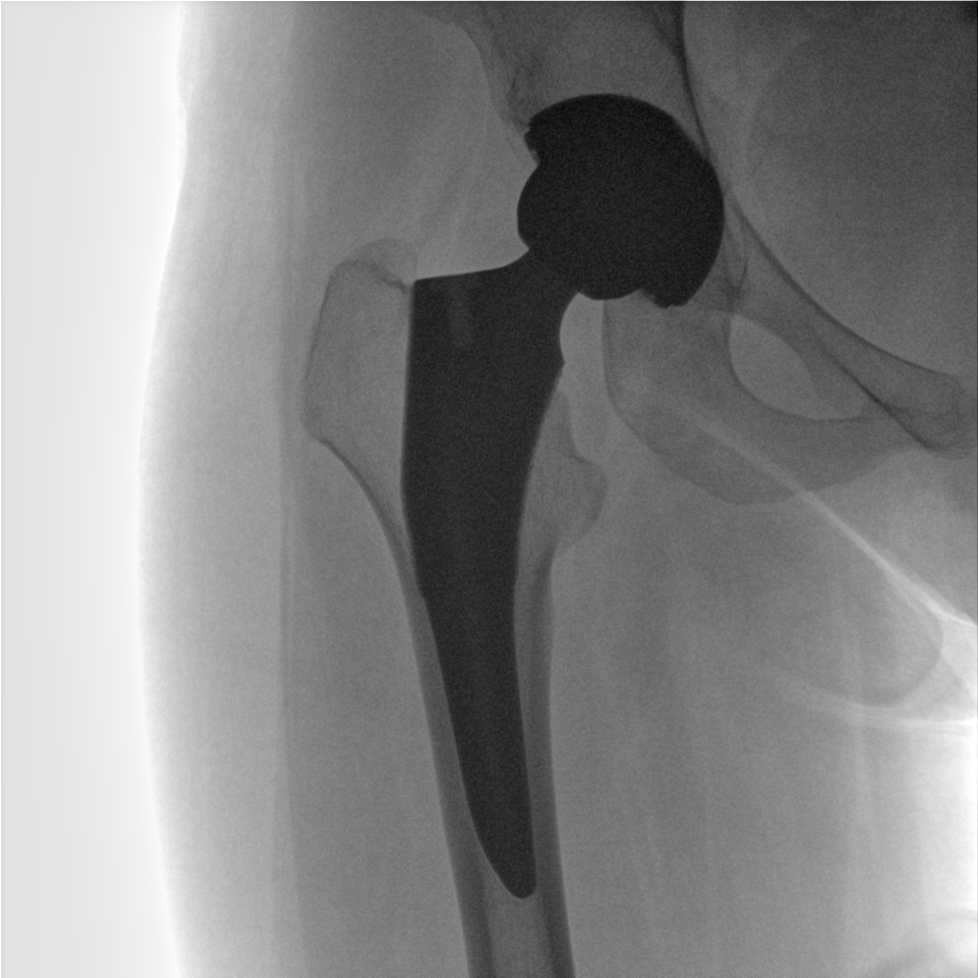

術(shù)中三維成像和橫斷面圖像提供多角度的手術(shù)診斷信息,輔助醫(yī)生進(jìn)行術(shù)中評估判斷,諸如骨折復(fù)位情況和內(nèi)植入螺釘?shù)某叽绾臀恢?,輔助手術(shù)更好地完成。

提供更大的術(shù)中三維成像視野,采集更多圖像信息,可一次拍全全段頸椎、全段腰椎、七節(jié)胸椎、雙側(cè)骶髂關(guān)節(jié)、股骨頭及單側(cè)盆骨。